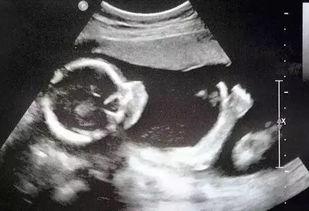

网友爆料医院b超室视频,网友曝光真实工作场景